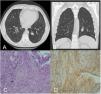

In view of this finding, a computed axial tomography (CT) scan of the thorax was performed, which confirmed the presence of a solitary pulmonary nodule measuring 2.2cm in the left lower lobe (LLL), with no evidence of other alterations (Fig. 1A, B).

(A, B) Computed axial tomography scan of the thorax, axial and coronal views showed a round, well delineated, 2.2cm nodule in the posterior segment of the left lower lobe. (C) Lung biopsy (haematoxylin and eosin stain; ×10) fusocellular and fasciculated stromal proliferation that traps pre-existing mucous-secretory glands. Characteristic histological features include cellular Antoni A. (D) Tumour cells were immunoreactive to S100.

Samples were sent to the pathology department, describing a bronchial mucosa occupied by a fusocellular and fasciculated stromal proliferation that traps pre-existing mucous-secretory glands inside and surround cartilaginous tissue (Fig. 1C). There was no atypia of significant mitotic activity, with minimal proliferative activity estimated with ki-67, around 1% of the cells. At the immunohistochemical level, they expressed only intensely and nuclear S-100 (protein found in cells derived from the neural crest, such as Schwann cells), being negative for Desmin, SMA, CD34, with non-valuable staining for CD10 (Fig. 1D).